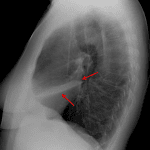

Findings

- Blurring of the right heart border on the PA projection with a triangular opacity seen overlying the cardiac silhouette on the lateral projection

Diagnosis

- Right middle lobe collapse

Right middle lobe collapse. Recommend followup imaging to ensure resolution. If there is persistent lobar collapse on followup imaging, chest CT should be obtained to assess for a fixed obstructive lesion.

- Right middle lobe collapse classically results in a triangular anterior opacity on the lateral view and hazy opacity with loss of the right heart border on frontal view

- Look for evidence of volume loss when trying to decide between atelectasis and consolidation. Signs of volume loss include hemidiaphragm elevation and hilar displacement toward the abnormality